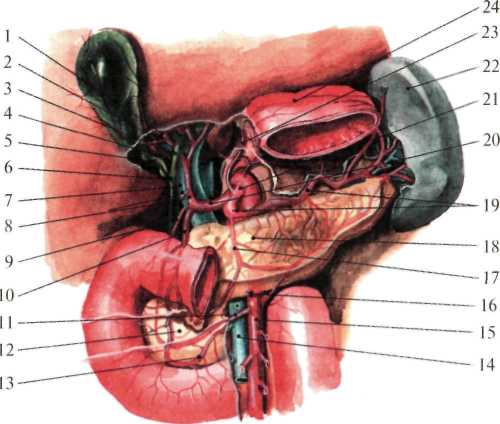

Рис. 1.27. Сосуды печени (по Неттеру, с изменениями).

1 — ramus dexter a. hepaticae propriae; 2 — a. cystica; 3 — ductus hepaticus communis;

4 — trigonum Callot; 5 — ductus cysticus; 6 — ductus choledochus; 7 — v. portae;

8 — a. hepatica propria et a. gastrica dextra; 9 — a. supraduodenalis; 10 — a. gastroduodenalis;

11 — a. pancreaticoduodenalis inferior; 12 — caput pancreatis; 13 — a. pancreaticoduodenalis inferior (ramus anterior); 14 — v. mesenterica superior; 15 — a. mesenterica superior; 16 — a. colica media;

17 — a. pancreatica dorsalis; 18 — pancreas; 19 — a. splenica; 20 — a. hepatica communis;

21 — truncus coeliacus;

Рис.1.29. Печеночно-дуоденальная связка и треугольник Кало (по Неттеру, с изменениями).

1 — lobus dexter hepatis; 2 — a. cystica; 3 — trigonum Callot; 4 — ductus cysticus; 5 — foramen omentale; 6 — ren dexter (ретроперитонеально); 7 — duodenum; 8 — fiexura coli dextra; 9 — omentum majus;

10 — flexura coli sinistra; 11 — lig. gastrocolicum; 12 — gaster; 13 — splen; 14 — omentum minus;

15 — v. portae; 16 — ductus choledochus; 17 — a. hepatica propria; 18 — ductus hepaticus;

19 — lobus sinister hepatis; 20 — lig. teres hepatis; 21 — lobus quadratus hepatis; 22 — vesica biliaris.